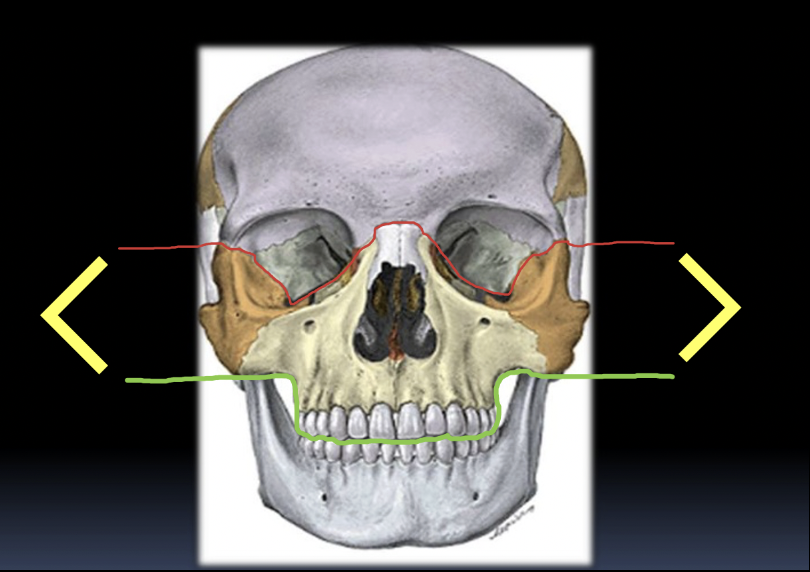

Fracturas maxilares: Le Fort

¿Qué son las fracturas de Le Fort?

A

Fracturas del tercio medio de la cara

- Se clasifican en 3 tipos: I, II y III

Le Fort I: horizontal

¿Qué describe la Le Fort II?

Maxilar flotante (trazo piramidal que separa maxilar del resto).

¿Qué describe la Le Fort III?

Desarticulación del neurocráneo del viscerocráneo (cráneo “flota” respecto a la cara)

# Fracturas maxilares: Le Fort **Tratamiento Qx típico** en **Le Fort**

* Fijación con aros de Erich * Mini-placas * Mini-tornillos * ≈1 mes de consolidación ## Footnote FIJACIÓN INTERMAXILAR